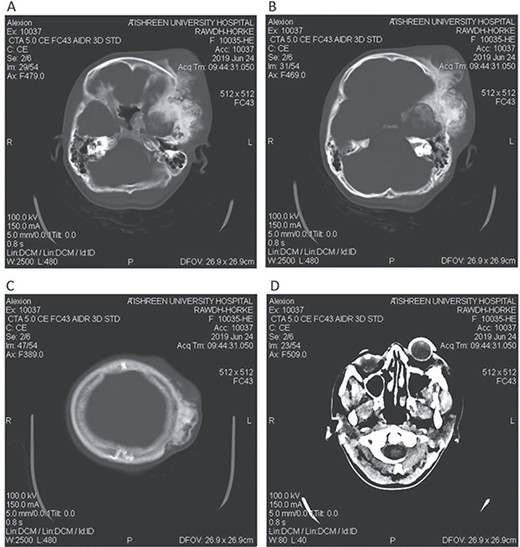

Postoperative CT head bone window (A–C). A. Regression of the pressure on the maxillary sinus. B. Decline of the exophthalmos. C. The parietal bone after excision of the masses. Tissue window (D). Regression of the pressure on left lateral ventricle and decline of the midline shift.

A 17-year-old female presented with a history of osteosarcoma that was confirmed after undergoing a surgery to remove an enlarging bone tumor in the left temporal region 2 years ago. She later got pregnant and delivered her child but never got back for a checkup until she was admitted to our hospital with a severe and unresponsive to medication headache that progressed over the course of 6 months and blurred vision that progressed to complete left-sided vision loss. Physical examination revealed a tough and mobile yet fixed at the base 7-cm mass towards the left of the frontal bone. Many more masses were revealed in the left side of the skull including the anterior cranial fossa, orbit, base of the skull and the left part of the occipital region where the previous procedure was performed (Fig. 1). These masses had been increasing in size probably under the influence of pregnancy hormones causing pain that radiated along the orbital and maxillary branches of the left trigeminal nerve. Physical examination and past medical history were otherwise unremarkable. Laboratory tests were all normal, and her family history was negative. Staging studies showed no evidence of distant metastatic disease in the chest, the abdomen and the pelvis. CT scan of the skull revealed a bone-forming non-lytic lesion accompanied by periosteal reaction. This lesion bulges to the outside towards the scalp spreading into both the soft tissues and the inside of the entire left side of the skull with a sunburst-pattern (Figs 2 and 3). Its rims are unsymmetrical and pointy, and it bulges into the left orbit outside the muscles causing exophthalmos with a semi-complete proptosis of the eyeball out of the orbit (Figs 2 and 3). This lesion applies pressure to the left frontal and temporal lobes causing mild edema in both these lobes without invading the brain tissue. This edema in turn applies pressure to the left lateral ventricles (minor shift of the elements of the midline to the right side can be seen on CT) (Fig. 4). Due to the tumor’s wide spread, the surgical procedure was performed in two stages (approximately 6-hour-long each). In the first stage, the bone mass was removed through a procedure of wide skull approach including the frontal, temporal and parietal bones and a removal of the invading part of the temporal muscle. Moreover, the lateral wall and roof of the left orbit were removed, the left optic nerve was dissected free and part of the meninges was removed and replaced with an autogenic patch from the fascia lata. Then, the bone loss was compensated for by using bone cement Synicem VTP (poly methyl methacrylate and Barium sulfate), and the orbit was rebuilt; the eyeball was placed back with noticeable decline of the exophthalmos. In the second stage, a complementary left parietal occipital incision of the previous approach was performed 3 weeks later; the remaining of the frontal and occipital bones was removed, and a partial mastoid surgery was done. Furthermore, the cavernous sinus were revealed and found to be not invaded. Later on, the normal skull shape was restored using the same cement. The histopathology of the lesion revealed proliferation of neoplastic chondroblasts, osteoblasts and spindle-shaped cells. The features are consistent with low-grade chondroblastic osteosarcoma (Fig. 5). The patient did not need ICU admission. She recovered well 3 days after the surgery and was discharged with no deficits. A CT scan that was performed post-operatively revealed that the masses were successfully excised (Figs 6 and 7). At the last follow-up 1 month post-operation, the patient was scheduled to undergo a course of radiotherapy, 60 Gy of radiotherapy in 30 fractions over 4 weeks without chemotherapy, as it is not recommended with low-grade osteosarcoma.